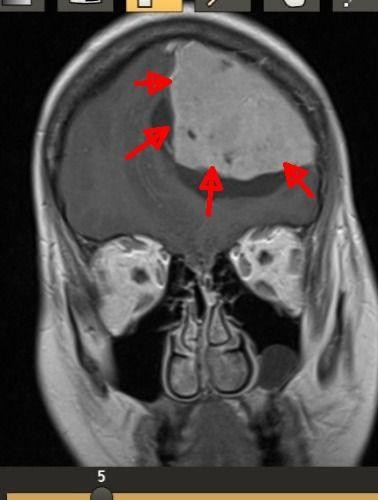

نجح فريق جراحة المخ والأعصاب في مستشفى الملك سلمان من استئصال ورم في الدماغ لسيدة ثلاثينية ، تعاني من صداعٍ شديد وغثيان مستمر ونوبات صرع.

وباشر الفريق الطبي بقيادة رئيس جراحة المخ والأعصاب د. عصام شبشوب إجراء عملية بالغة الدقة استغرقت حوالي 4 ساعات، تم خلالها الاستئصال الكلي للورم مع الحفاظ على سلامة الوظائف العصبية للمراكز الدماغية الحساسة المتاخمة للورم مثل مراكز التحكم في النطق والحركة؛ وذلك عبر استخدام تقنيات جراحية دقيقة وأجهزة متطورة مثل جهاز تفتيت وشفط الأورام بالموجات فوق الصوتية، وتمت إفاقة المريضة من التخدير مباشرة بعد العملية وهي لا تزال في غرفة العمليات، وكانت متجاوبة وبدون وجود أي مضاعفات ، وهي الان في طور التحسن المستمر ولله الحمد .